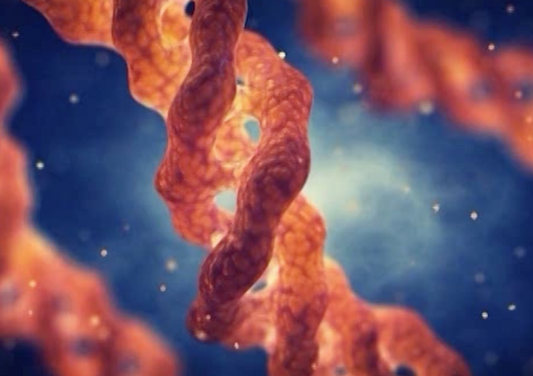

Cancer Cliff Notes - Ce que vous devez savoir

Ce qui est Nouveau dans le Cancer

Trucs et Astuces pour le Lymphome chez les Chiens